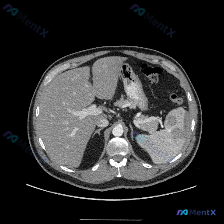

整理了一张很有讨论价值的上腹部平扫CT病例,先把核心信息和我的分析思路放出来: 📋 核心影像表现 图像显示的是上腹部层面,除脾脏外,肝实质、胰腺、胃壁、腹主动脉及腹膜腔在该层面均未见明显异常。唯一的显著异常在脾脏: - 脾脏实质内可见明显的低密度区域 - 边界尚清,但形态欠规则 - 位于脾脏实质内部...

看到一份腹部CT的单幅影像分析,关于脾脏的这个病灶,觉得很有讨论价值,整理一下思路和大家分享。 --- 先看影像给出的客观发现 - 基本情况:单幅腹部CT横断面(层面未全,仅看所示范围) - 阳性表现: 1. 脾脏实质内见一类圆形低密度灶,边界尚清晰,内部密度均匀 2. 病灶CT值近似水样密度 3....

看到一份很有意思的腹部CT平扫图像,主要焦点在脾脏,整理了一下思路分享给大家。 --- 影像核心发现 这是一张横断面腹部CT软组织窗的图像: - 肝脏、血管、腹膜后间隙等其他结构在该层面未见明确异常; - 脾脏:大小形态正常,但实质内可见一个类圆形病灶,界限比较清晰; - 关键特征:外周呈高密度环状...

整理了一份脾脏多发低密度灶的CT读片和分析思路,这个病例其实很容易被“边界清”带偏,先把关键信息和我的思考过程放出来: 影像核心发现 单张上腹部CT横断面(软组织窗): - 肝脏、腹主动脉、下腔静脉等周围结构大致正常 - 脾脏实质内见数个类圆形低密度灶,边界相对清晰 - 无明显渗出、炎症或肿大淋巴结...